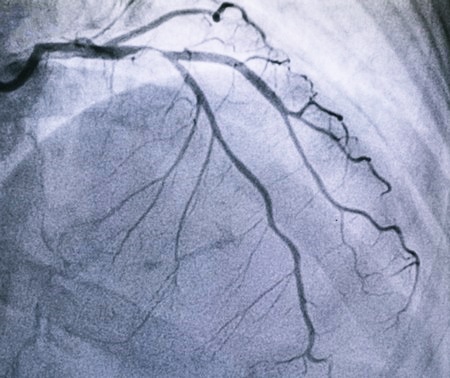

Ангиография сосудов – это метод исследования сосудов с помощью рентгеновского излучения. Термин в более узком смысле означает скиографическое отображение артерий после заполнения контрастным веществом. Визуализация должна проводиться как минимум в 2-х рентгеновских проекциях, т.к. стеноз может быть асимметричным, отсутствовать в одной проекции.

- коронарография сосудов головного мозга и сердца (изображение коронарного русла, сосудов, питающих сердце, мозг).

Ангиография может хорошо визуализировать сосудистые заболевания, такие как сужение артерии из-за атеросклероза или аневризму (выпуклость).

После установки проводника врач обычно вводит в артерию пластиковую трубку, через которую можно вставить инструменты; утечку крови из сосуда предотвращает предохранитель. Затем в нужную область через трубку вводится рентгеновский катетер – во время обследования врач контролирует его на рентгеновском экране. Через катетер в исследуемую область попадает контрастное вещество. Оно поглощает рентгеновские лучи, и поэтому точки, через которые они проходят, видны на рентгеновском изображении. Врач контролирует рентгеновское изображение на экране и, таким образом, может определить сужение кровеносных сосудов или места, из которых контрастное вещество просачивается в ткани.